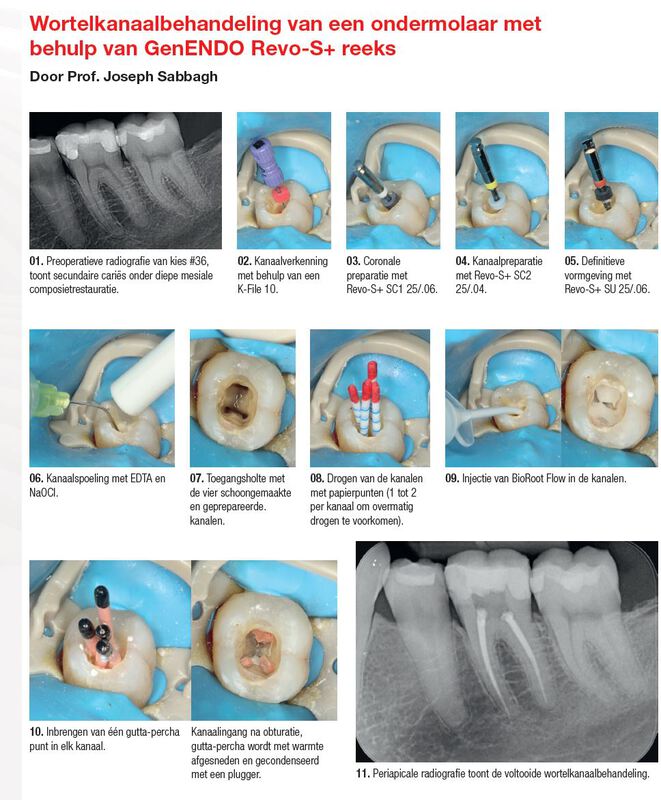

GenENDO K-Files

ISO-kleurcodering

Radiopaak siliconen stopring

008/.02, 010/.02, 015/.02

Verkrijgbaar in 3 lengtes (21, 25, 31 mm)